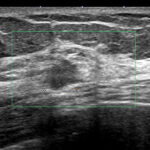

これが検診時の画像

私カテゴリーでは「私cat.6 乳癌の可能性がかなり高い」

例)スピキュラはないけど不整形、境界不明瞭

♯ちなみに一般的なカテゴリー(1~5)では4となります。